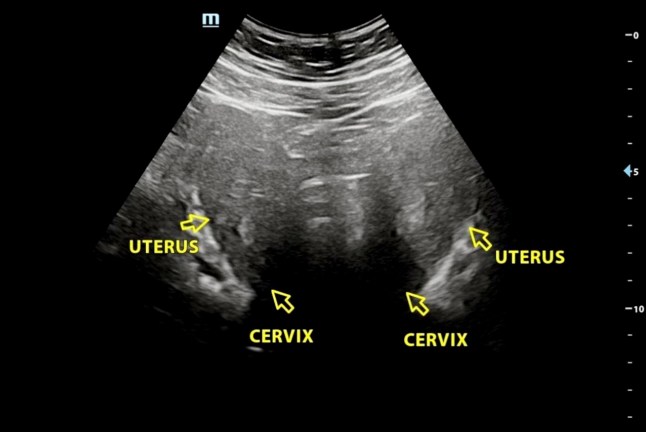

An ultrasound scan of Ellie Curran's two wombs - Ellie Curran who had to go to the toilet "every two seconds" while on her period discovered it's because her womb is split in half. // The medical condition ? called complete bicorporeal uterus ? occurs where the uterus has a deep external indentation at the top which creates two distinct heart-shaped uterine cavities that are fully separated by a wall of tissue. Ellie Curran, 21, first started experiencing intense pain when she started her period aged 12. Alongside ?leaking? through sanitary products she has found herself unable to ?leave the house? due to the intensity of the pain ? and received a diagnosis of PMDD ? Premenstrual Dysphoric Disorder ? in November 2025. Doctors removed her appendix when she was 19 due to her stomach pain but found it had not ruptured. During the surgery they found what they believed to be an extra womb and Ellie was referred to a women?s clinic. After further scans doctors ?didn?t know for sure? whether Ellie?s uterus was completely split into two ? Uterus Didelphys ? or was one uterus that had an indentation, called a Bicoporeal Uterus. Photo released 23/01/2026

An ultrasound scan of Ellie Curran’s two wombs, formed by a big indentation at the top of the uterus (Picture: Oh Baby Ultrasound Clinic / SWNS)